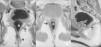

ResultadosEn 6 de los 12 pacientes estudiados los músculos elevadores del ano y complejo esfinteriano presentaban grosor y simetría dentro de la normalidad con un adecuado posicionamiento del neorrecto respecto al complejo esfinteriano en cinco de ellos (fig. 2). En un caso se observó que el anorrecto descendido se situaba por fuera del complejo esfinteriano lo que justificaba la incontinencia anal a pesar del buen desarrollo del complejo muscular estriado (elevador del ano y esfínteres) (fig. 3).

Paciente con ARPSP. Adecuado posicionamiento del neorrecto descendido (R) respecto al complejo muscular estriado, elevadores del ano (flecha) y complejo esfinteriano (cabeza de flecha), el cual presenta un grado normal de desarrollo. Planos coronal (A), axial (B) y sagital (C) potenciados en T1.